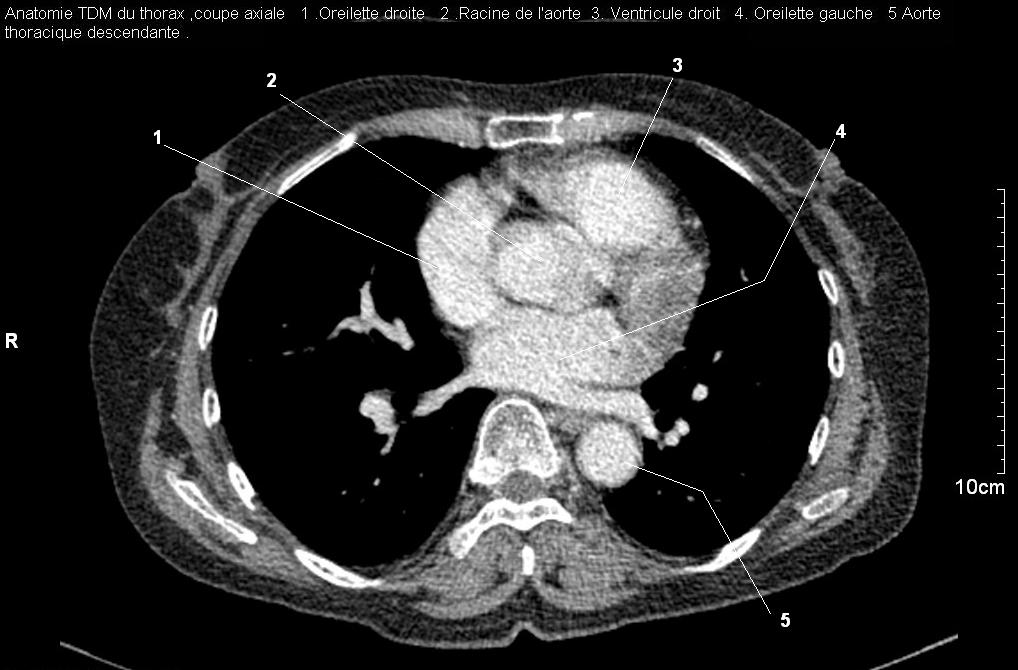

Radioanatomie pulmonaire ( image radiologie

thoracique normale )- La Tomodensitometrie du thorax (

coupes axiales fenetre mediastinale ) |

Les fenetres mediastinales permettre

d'etudier anatomie du mediastin et les structures vasculaires

en coupes axiales de 0,5-1cm sur le thorax . Et si elles

sont opacifiees par produit de contrast elles sera se donnent des resutats

suivantes : |